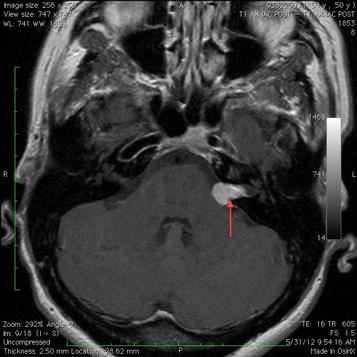

All of the aforementioned causes of hearing loss can lead to tinnitus. Acoustic neuroma also known as vestibular schwannoma is a noncancerous and usually slow growing tumor that develops on the main vestibular nerve leading from your inner ear to your brain. As it grows it can also interfere with the facial sensation nerve the trigeminal nerve causing facial numbness. The acoustic neuroma is the most common tumor of the cerebellopontine angle.

As the acoustic neuroma grows it compresses the hearing and balance nerves usually causing unilateral one sided hearing loss tinnitus ringing in the ear and dizziness or loss of balance. The most common presenting symptoms are unilateral sensorineural hearing loss tinnitus and imbalance. It grows slowly from an overproduction of schwann cells and is also called a vestibular schwannoma. Acoustic neuroma is a rare noncancerous tumor.